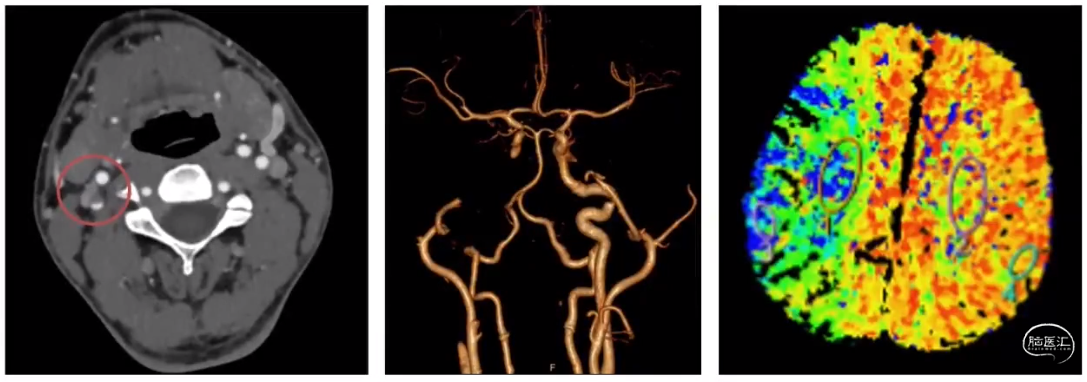

病例示例

患者女性,22岁,因左眼视力进行性下降,右侧肢体无力进行性加重1个月入院。患者仅能平卧,左眼无光感,右侧肢体肌力四级(宣武医院病例)

术中可以看到动脉中膜和内膜长到了一起,外膜也明显增厚,整个动脉管壁均匀增厚变白,管腔还在,但很细,腔内还有白色质韧的结缔组织,连有少许陈旧血栓。